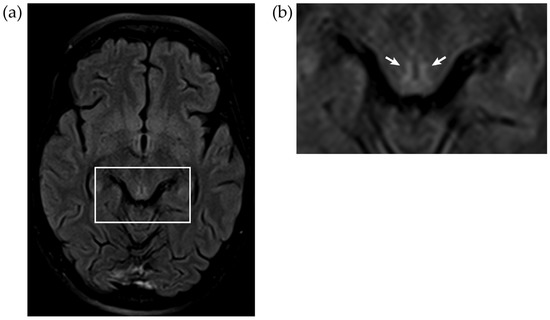

3.5. Imaging